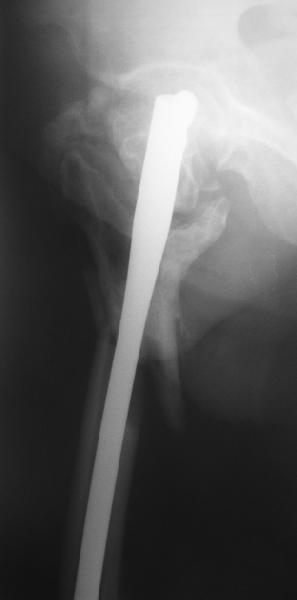

На прошлой неделе оперировали похожего пациента. 2 года после неудачного остеосинтеза PFN в другом регионе. После удаления остатков железа выявилось несращение вертельной области.

В такой ситуации важно устранить варусную деформацию. При использовании гвоздя это непросто. Поэтому в число рассматриваемых

вариантов стоило бы включить вальгизирующую остеотомию с фиксацией 130-градусной клинковой пластиной или DHS.

Если есть сильное желание фиксировать все-таки гвоздем, советовал бы ввести мощный "джойстик" параллельно оси шейки бедра близко к ее задней стенке, сделать поперечную межвертельную остеотомию и использовать дистрактор таз-бедро.

Поскольку в нашем случае выявилась подвижность, мы наложили дистрактор таз-бедро на 3 дня, и сделали остеосинтез гаммой без остеотомии. То, что произошла "корригирующая остеоклазия" в подвертельной области, выявили после введения гвоздя. Пациент уже уехал домой, будем наблюдать.